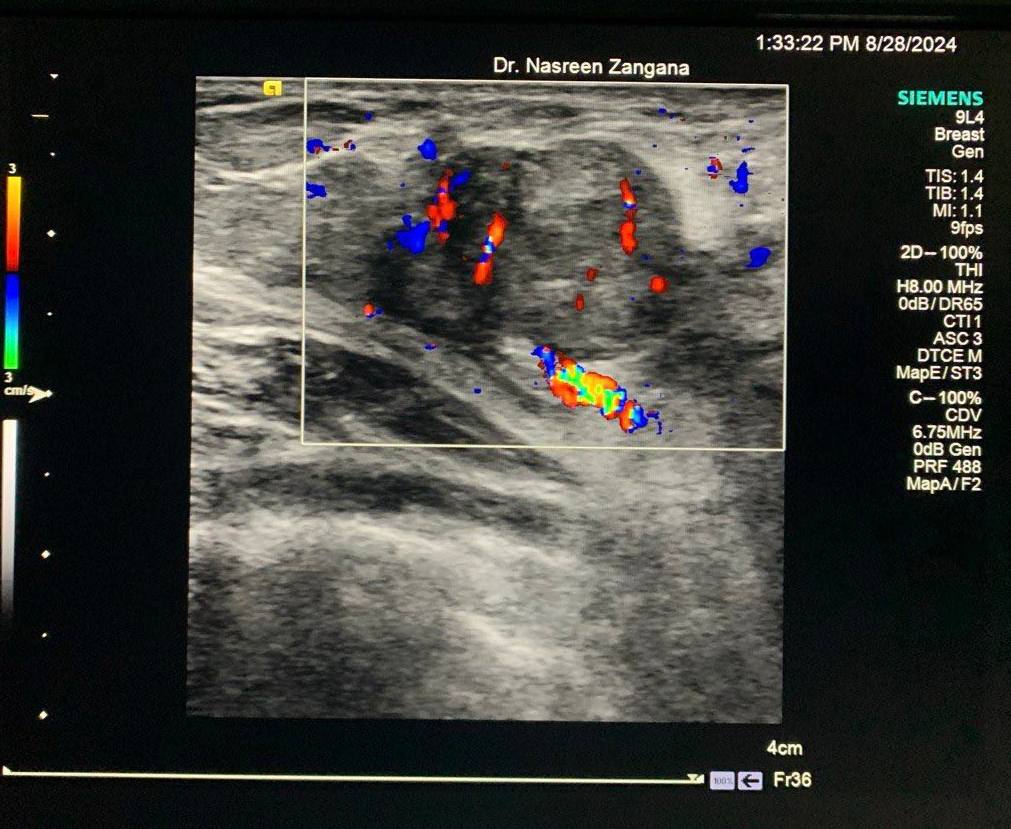

Breast U/S

Hypoechoic vascular solid mass at left axilla ectopic gladular breast tissue of lactating woman, lactating adenoma? fibroadenoma ?